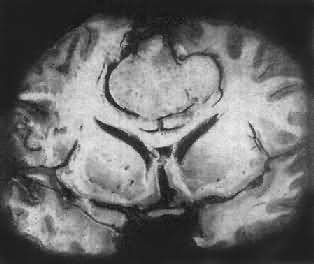

肉眼观,肿瘤为数厘米的结节至巨大块状。分化较好的肿瘤,境界不清;而分化程度较低的肿瘤则境界分明。瘤体灰白色。质地视肿瘤内胶质纤维多少而异,或硬、或软、或呈胶冻状外观,并可形成大小不等的囊腔。由于肿瘤的生长、占位和邻近脑细胞的肿胀,脑的原有结构因受挤压而扭曲变形(图16-23)。

星形胶质细胞瘤

图16-23 星形胶质细胞瘤

大脑半球肿胀,肿瘤边界不清,部分呈胶冻状